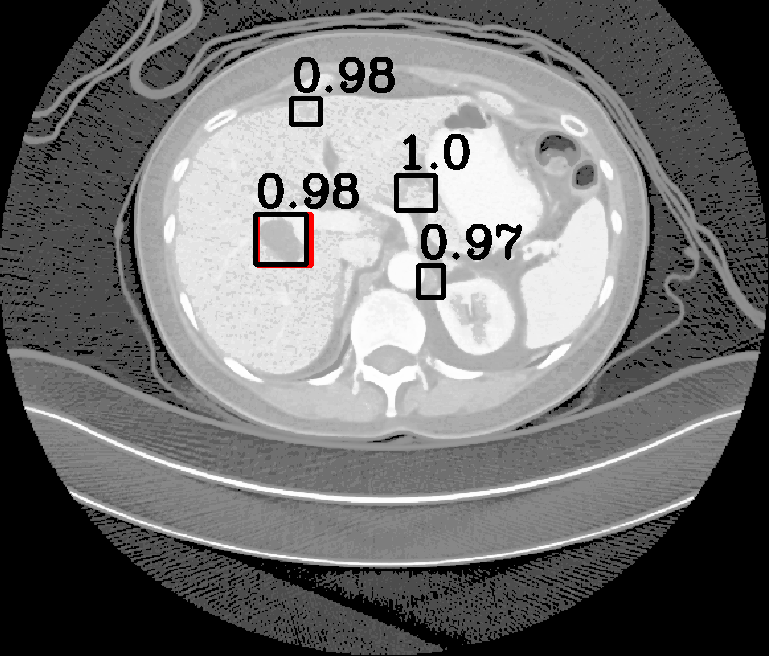

| (a) Ground Truth | (b) Faster R-CNN | (c) FPN | (d) Proposed |

In real-world scenarios, body lesions usually have arbitrary size. For instance, in the DeepLesion [14] dataset, the lesion size ranges from 0.21 mm to 342.5 mm. Since most of the established CNNs are not robust to handle such spatial scale variations, they have unpredictable behavior in the varying cases. As shown in Fig. 1, both Faster R-CNN and FPN fail to detect tiny lesions in the first row, while they produce small false positive lesions around the actual large lesion locations in the second and third rows.